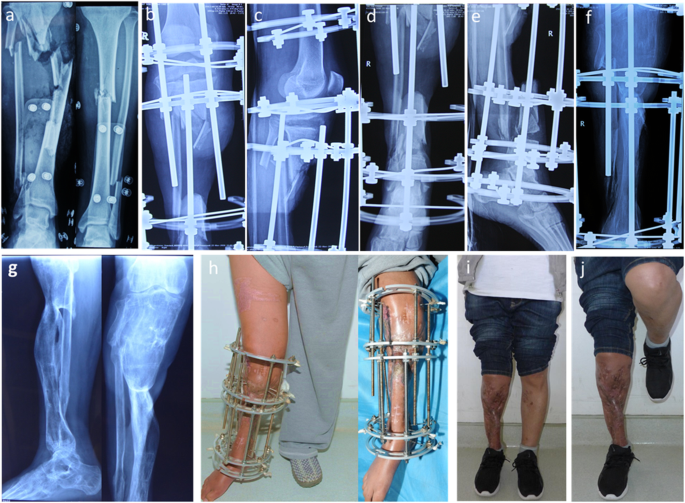

a Radiograph of case no. 31 who was involved in a traffic accident resulting in right tibia open fracture and Gustilo IIIB. b-e After three previous debridement operations, there was a defect of 18.2 cm on the tibia, and the proximal and distal osteotomy was performed. The osteotomy sites were obviously shown on the X-rays. f Radiograph of transport bone segment reaching docking site 30 months after osteotomy. g Union was achieved both in docking site and elongation area 35 months post-operatively. h Soft tissue defect was closed during the process of bone transport 5.8 months after osteotomy. i-j Complete bone and soft tissue union was achieved and frame was removed 35 months after osteotomy